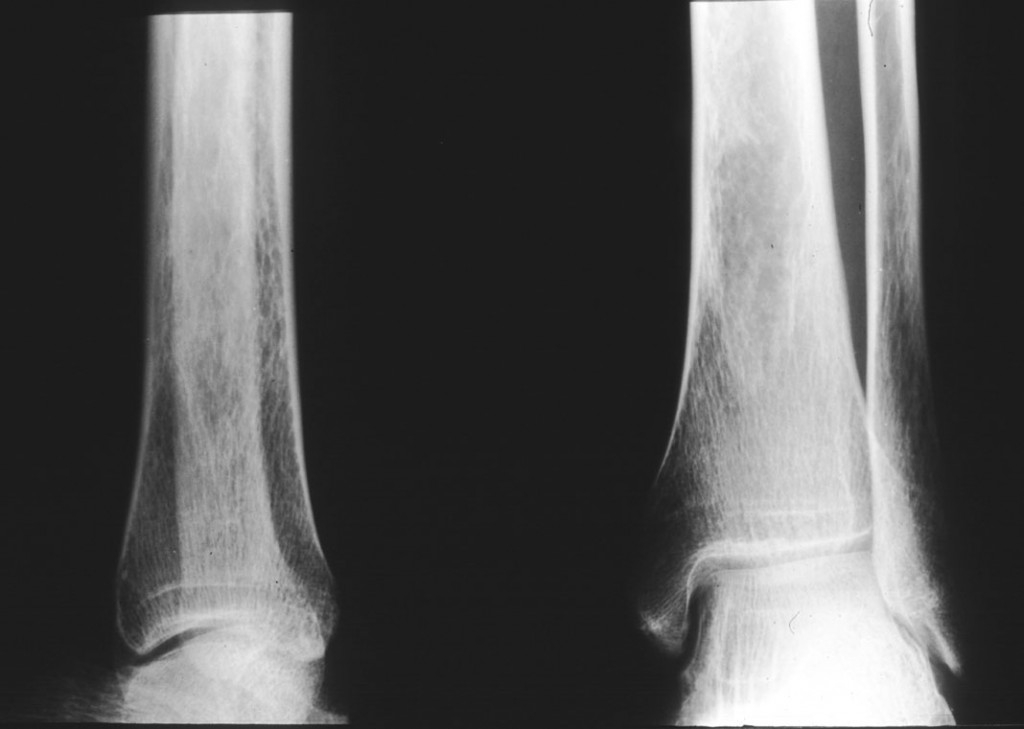

Test de osteoporoză

Osteoporoza este o boală care apare după menopauză şi care ameninţă una din două femei trecute de 50 de ani. Practic, oasele pierd foarte mult din densitatea normală, devenind astfel fragile. Pot apărea din acest motiv fracturi destul de severe. Un simplu test de măsurare a densităţii osoase poate ajuta la preîntâmpinarea osteoporozei.